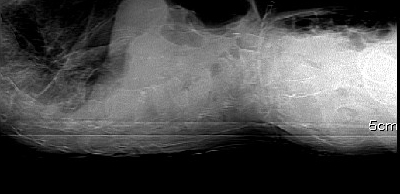

标题: CT8424:男,89岁因外伤后2天胸腰椎CT平扫. [打印本页]

标题: CT8424:男,89岁因外伤后2天胸腰椎CT平扫.

男:89岁因外伤后2天行ct检查。请各位战友讨论图中所指是否是骨折和形成该影像的原因(扫描层面位于椎体中份)。

椎体压缩性骨折,结肠淤张,胀气说明肯定骨折.

椎体压缩骨折,结肠淤张,应该肯定,交感神经有损伤.

老年性骨质疏松,椎体前缘出现双边征支持压缩骨折。椎体骨质稀疏,似有破坏,警惕溶骨性骨转移。

一定要结合定位像.

椎体前缘双边征,其后椎体内密度增高均提示压缩性骨折

压缩性骨折,骨质疏松,前缘密度增高,考虑压缩所致

椎体前缘呈双边征 考虑 压缩性骨折,椎体退行性病变。

说实话,我发布该病例的目的是大家在日常工作经常遇到的,由于现在的医患关系好处理,在写报告时遇到类似问题一定要小心.

我的报告1:腰椎骨质退行性改变。

2:t12改变考虑压缩骨折?请结合临床。